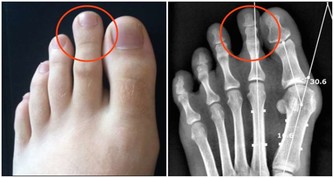

2年前,小羅右腳腳底突然長出一顆黑痣,一開始沒什麼感覺,但是隨著時間越長越大,到當地醫院檢查,醫生認為這是長雞眼,開了點藥膏給小羅。但塗了藥膏,黑痣絲毫不減消退,反而會凸起來,走路還硌腳,會痛。

另外,長在手掌、腳底、腰部​周圍、腹股溝、腋下等部位的痣也會更危險,因為這些部位更容易被摩擦,在長期的刺激下痣容易發生破損、潰爛等,惡變的可能性也就更大。如果是這些部位的痣,建議及時到醫院切除。